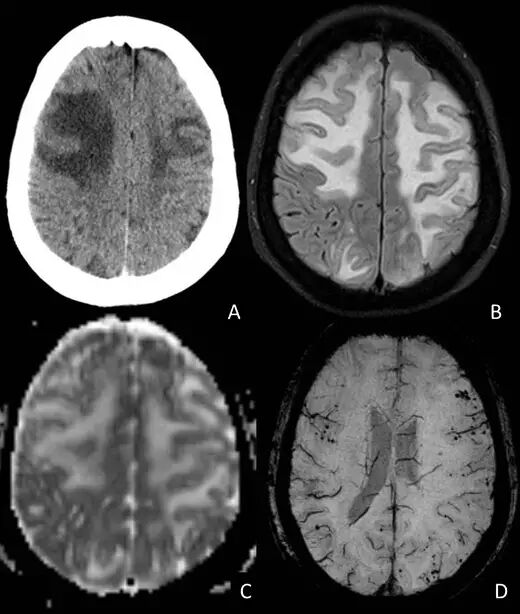

CT平扫可提示皮质下广泛低密度病灶,通常累及颞叶或额叶。几乎所有患者的MRI均异常,主要表现为T2或FLAIR上单发或多发的白质高信号,可伴水肿,病灶常为非对称性,可散在分布或融合成片或呈肿瘤样伴占位效应,灰质较少累及T2*WI上绝大多数患者存在皮质-皮质下微出血,部分患者皮质-皮质下既有微出血又有大出血,只有少数患者表现为大出血。约50%患者有脑白质疏松表现,50%患者有脑膜轻度增强。脑血管造影可见约22%患者存在轻度的双侧脑血管狭窄,主要是大脑中动脉、大脑前动脉的小分支。

(78岁女性,表现为快速进展性痴呆。A:最初的CT可见双侧额叶皮质下大片低密度病灶;B:FLAIR上弥漫病灶呈高信号;C:ADC未见弥散受限;D:SWI证实双侧大脑半球皮质-皮质下多发微出血)